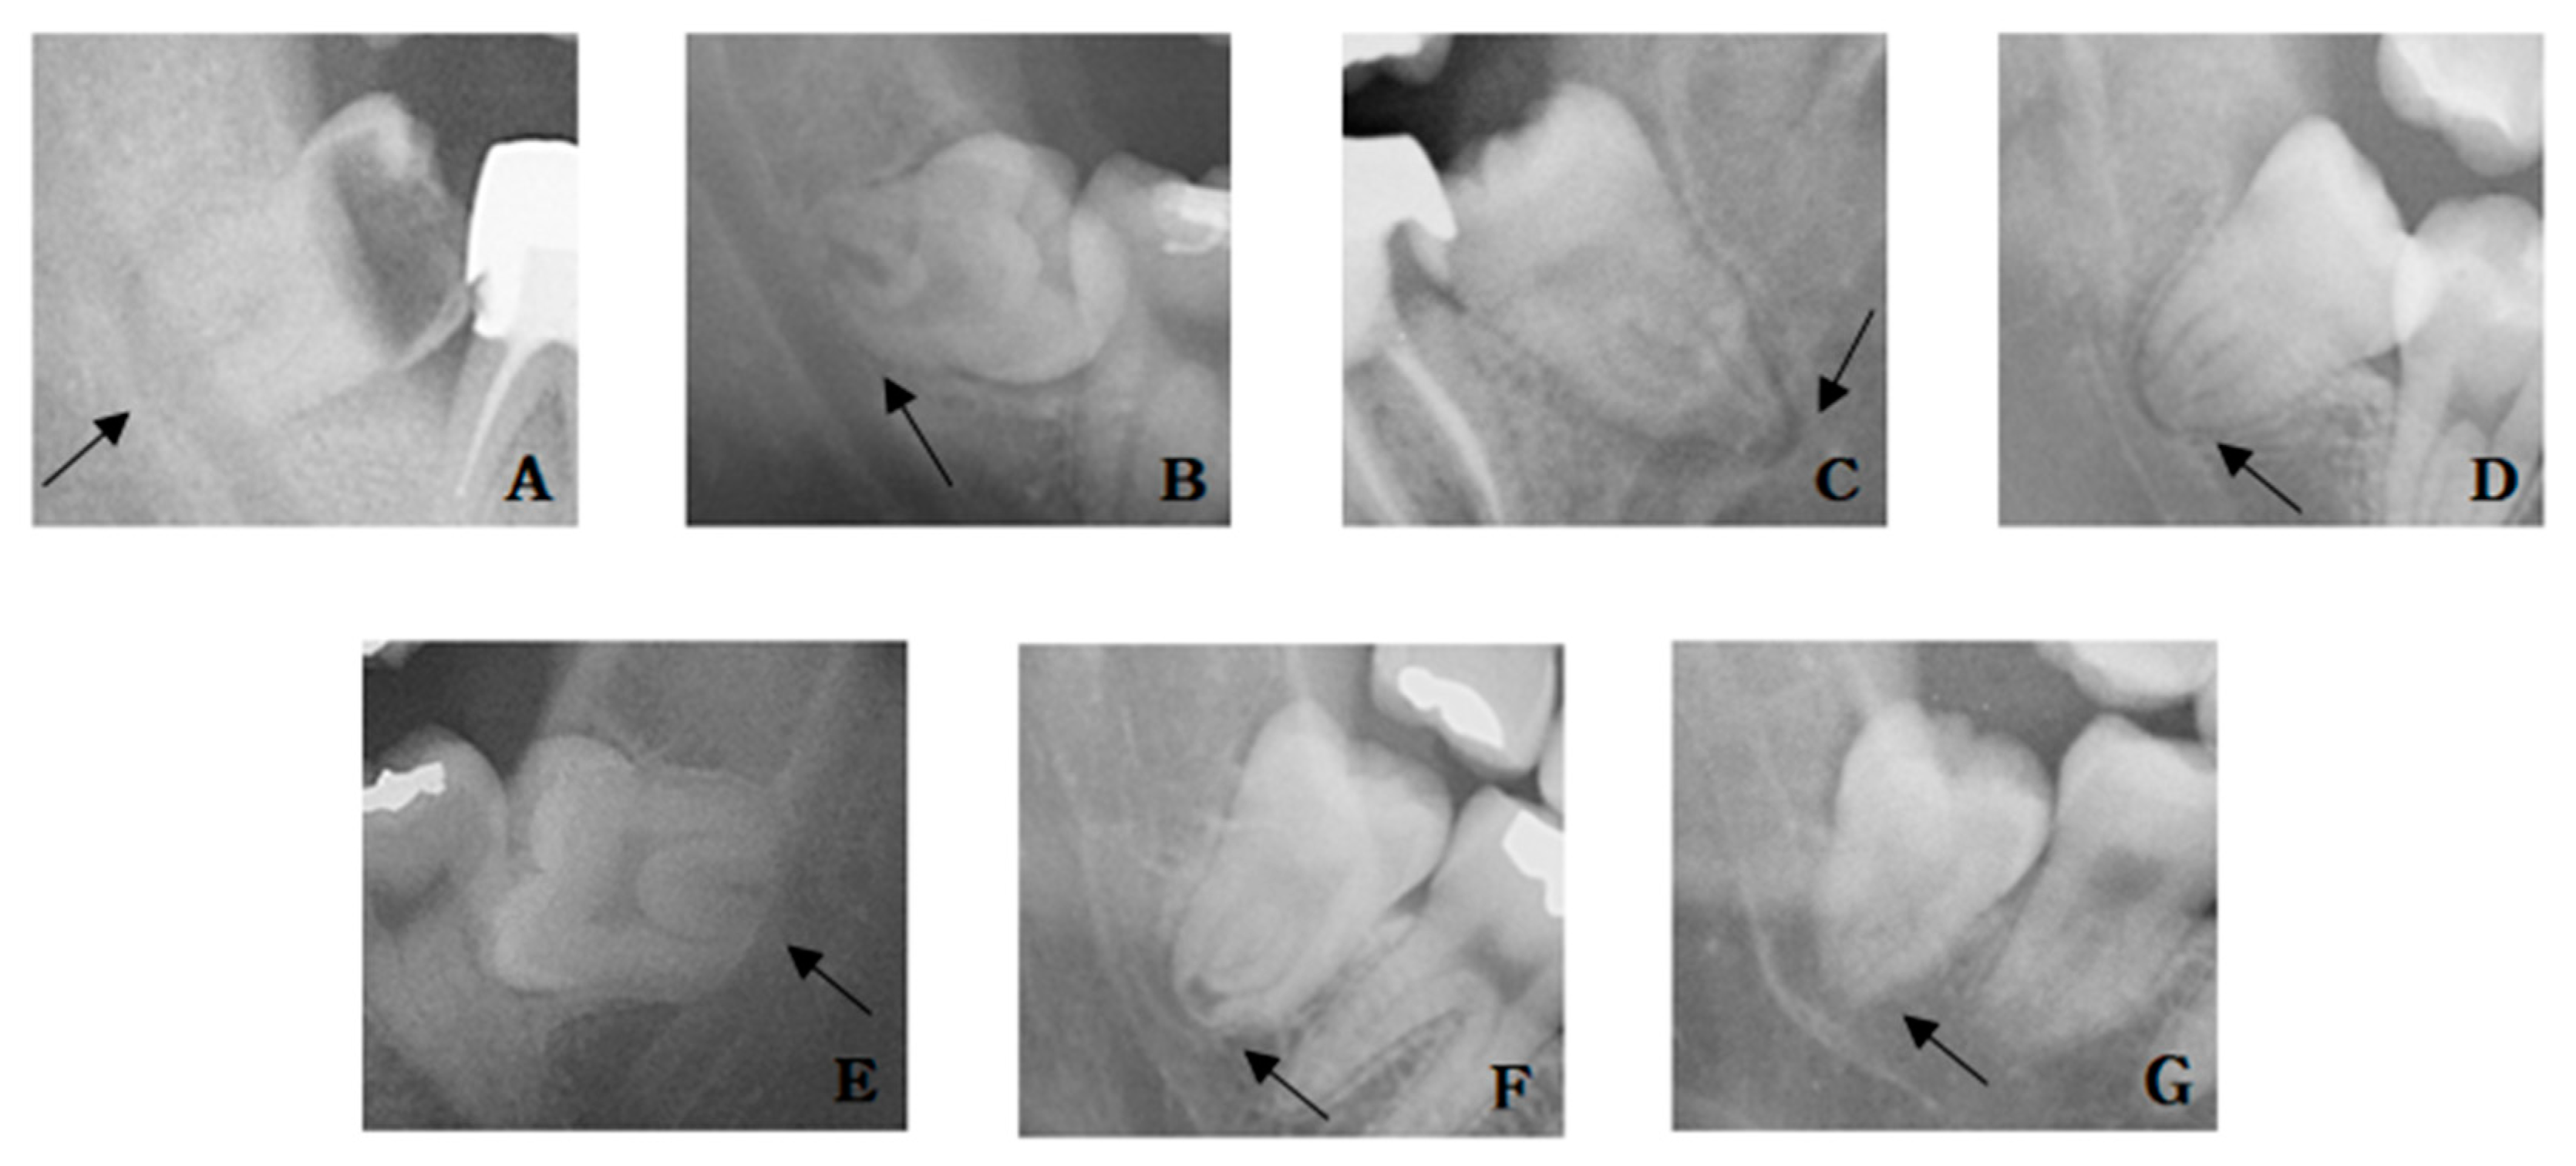

The relationship between the IAN and the mandibular third molar root was observed on panoramic radiography. Based on seven radiographic signs suggested by Rood and Shehab [20], darkening and bifid of the root apex at the IAN area was included as the case of darkening of the root because it was not easy to distinguish. In addition, there were cases where the dark line is visible at the root apex, and this case was also investigated. The radiographic signs were divided into a total of seven observations (Figure 3 and Figure 4): (1) cases where the root was darkened in the IAN area, (2) cases where the root was curved at the IAN area, (3) cases where the root was narrowed in the IAN area, (4) cases with a dark line at the root apex, (5) cases with the loss of the white line of the IAN at the root area, (6) cases with a narrowed IAN at the root area, and (7) cases with a change in the pathway of the IAN at the root area.

Figure 3. Rood and Shehab classification of radiographic signs: (A) root darkening, (B) root deflection, (C) root narrowing, (D) dark line in apex, (E) loss of white line, (F) inferior alveolar nerve (IAN) narrowing, and (G) IAN diversion.

Figure 4. Panoramic view. Arrows indicated the panoramic signs: (A) root darkening, (B) root deflection, (C) root narrowing, (D) dark line in apex, (E) loss of white line, (F) inferior alveolar nerve (IAN) narrowing, and (G) IAN diversion.